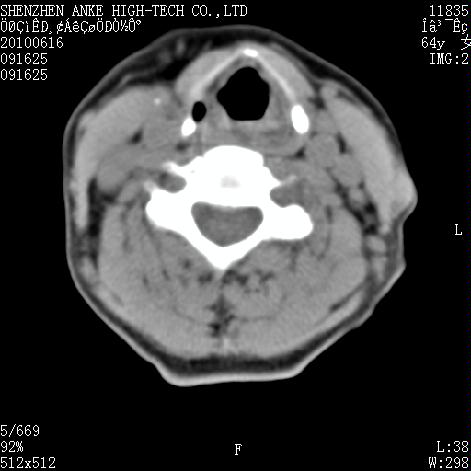

标题: CT27132:患者女,64岁,颈部及全身多处包块,现觉吞咽困难4 [打印本页]

标题: CT27132:患者女,64岁,颈部及全身多处包块,现觉吞咽困难4

右侧甲状腺占位,肿瘤可能性大,癌

右侧甲状腺癌伴右颌下腺淋巴结转移

右侧甲状腺癌伴淋巴结转移

右侧甲状腺癌伴淋巴结转移可能性大

右侧甲状腺癌伴淋巴结转移可能性大。

右侧甲状腺癌伴右颌下腺淋巴结转移!建议增强!